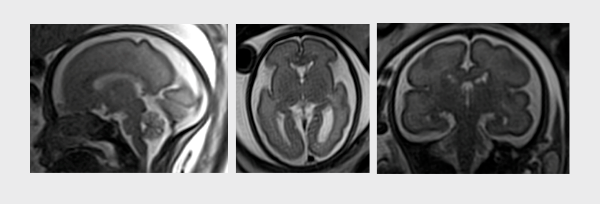

A avaliação do sistema nervoso central fetal (cérebro e medula espinhal) durante o período gestacional é muito importante e complexo. O desenvolvimento do sistema nervoso central do feto é dinâmico, uma longo e extraordinária jornada até a sua completa formação. Avaliar este desenvolvimento durante o período gestacional é desafiador e realizado pelos médicos especialistas em medicina fetal através dos exames de ultrassonografia morfológica do feto. Apesar do constante avanço e aprimoramento dos exames de ultrassom, tanto tecnológicos quanto dos profissionais dedicados exclusivamente a medicina fetal, a ressonância magnética é um método auxiliar muito importante em algumas situações durante este acompanhamento. O desenvolvimento tecnológico exponencial do exame de ressonância magnética permite a realização de exames seguro para a mãe e para o feto, de forma rápida e com um minucioso detalhamento e visualização de todas as estruturas do cérebro do feto.

- Durante o exame diversas imagens são realizadas do feto, com a minuciosa avaliação de cada estrutura cerebral.